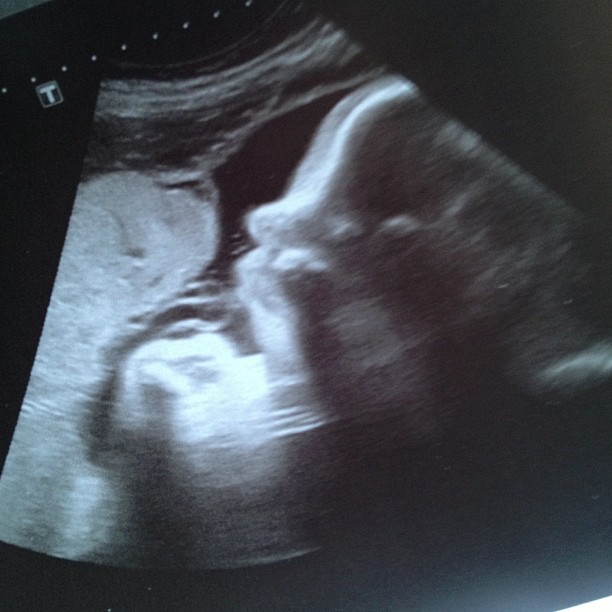

When I had my weekly checkup last Thursday, the doctor requested another ultrasound to measure baby boy’s size. If you have been reading my updates for a while, you’ll remember that a few weeks ago I was measuring four weeks ahead of schedule according to my belly size. When we had that ultrasound, they changed baby boys due date from November 26 to November 19. Since we’re nearing the end of my pregnancy, the doctor decided to go ahead withanother ultrasound to see if he was still measuring bigger than he should.

We had that ultrasound today. Jonah is currently measuring about 38 weeks and 4 days. So we’re somewhat back on schedule and where we are supposed to be. According to this ultrasound, my due date would be November 24; only two days different than the original due date they gave us. Everything with our sweet boy was measuring as it should. His lungs, heart, and other little body parts are all developed and are showing no signs of having any issues. We watched him breathing and flexing his little hands and fists. His guesstimated weight right now is about 7.5 pounds. Which puts him already almost a pound larger than his brother (assuming that the weight is accurate).